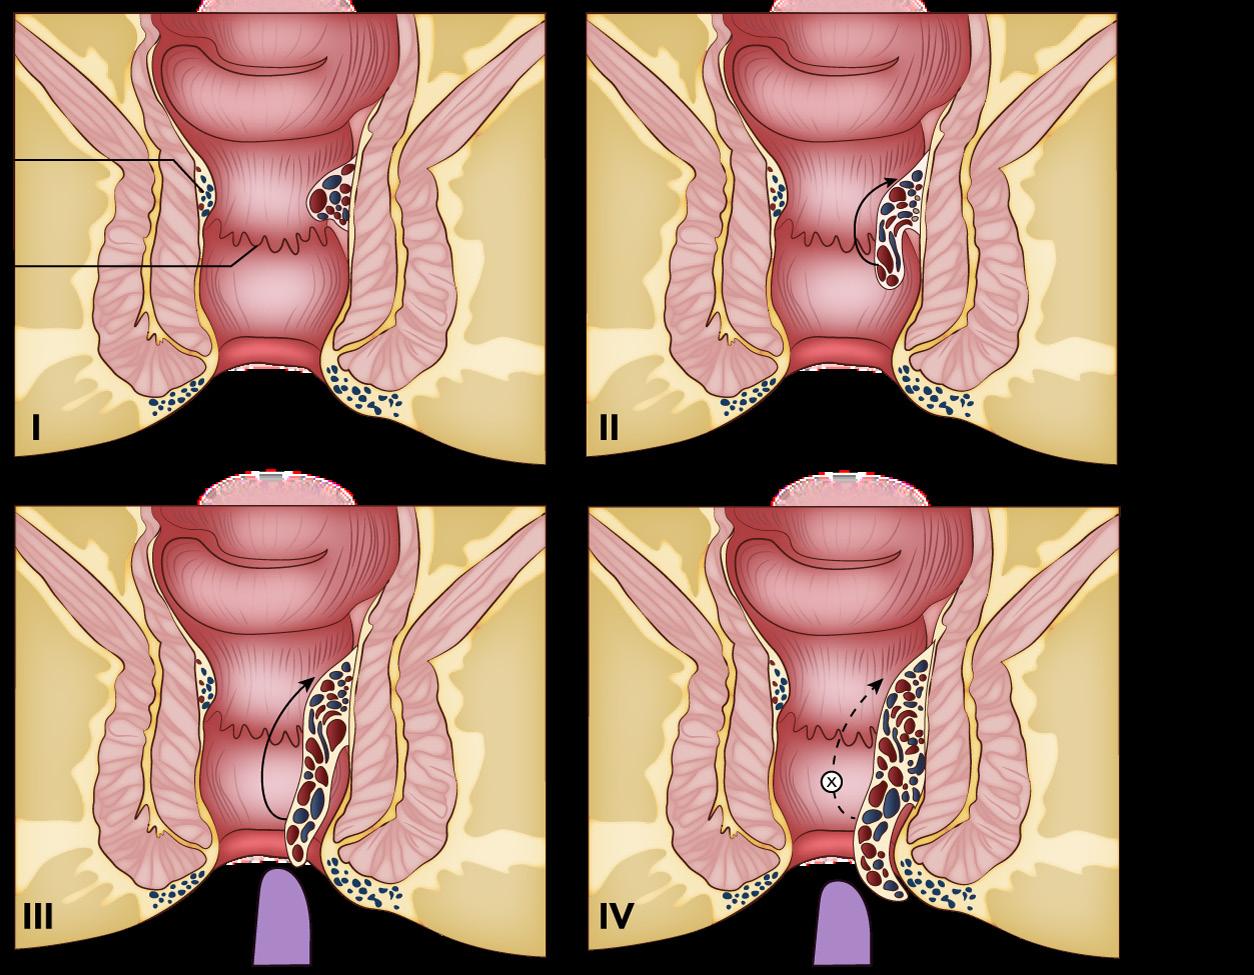

En caso de las hemorroides internas (clasificación de Goligher) (ESSALUD 2004)

Grado I: las hemorroides no se prolapsan, son reversibles, se ubican por encima de la línea dentada y pueden visualizarse en la anoscopia

Grado II: prolapso de hemorroides con esfuerzo, pero se reducen espontáneamente

Grado III: prolapso de hemorroides con esfuerzo y solo se pueden reducir manualmente

Grado IV: prolapso irreducible

Tratamiento

GRADOS CLÍNICA MANEJO

I

II

III

• Sangrado (ENARM 2011)

• No hay prolapso

• Sangrado

• Prolapso con reducción espontánea

• Prolapso con reducción manual

• No se reduce.

IV

• Puede generar estrangulamiento (trombosis) que se traduce en una masa violácea dura que genera intenso dolor.

Baños de asiento + dieta rica en fibra

Ligadura con bandas elásticas/ fotocoagulación + escleroterapia (ENARM 2020)

Cirugía: Hemorroidectomía cerrada (ENARM 2017) (ESSALUD 2007)

Cirugía: Hemorroidectomía abierta (ENARM 2015, ENARM 2016)

En casos de trombosis el manejo inicial es drenaje seguido de cirugía (ENARM 2011, ENARM 2015) (ESSALUD 2016)

Figura 54.. Hemorroides internas (clasificación de Goligher)